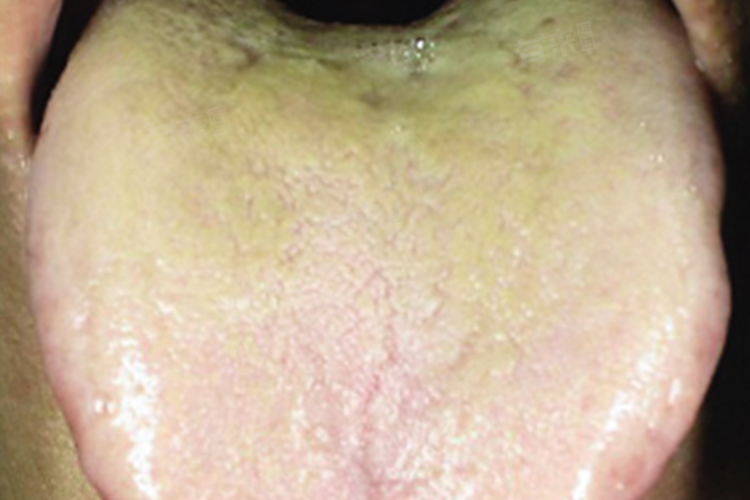

舌苔发黄厚腻,可能是湿热积滞、积食化热、肝火旺盛等引发的,需要根据自身情况,在医生指导下进行针对性治疗,如药物调理,改善自身不适症状。

1、湿热积滞:生活环境过于潮湿,感受湿热之邪,或是过度思虑、情志不畅等因素,引起湿热积滞,会出现腹痛、恶心、呕吐、口苦等症状,可有舌苔黄腻、脉弦数表现,可遵医嘱使用药物进行调理。

2、积食化热:如果经常暴饮暴食,或是过食生冷、刺激的食物,导致食物堆积在胃内不能及时消化,长此以往会导致脾胃虚弱、脾失健运,也可出现此现象,伴有腹胀、食欲不振、嗳气等。建议在医生指导下使用药物进行治疗。

3、肝火旺盛:多是由于情志不畅、生活不规律等因素引起,肝火上升,会有视物模糊、眼部分泌物增多、耳鸣、易怒等表现,可观察舌苔有上述改变,可以在医生建议下使用中成药等药物进行治疗。